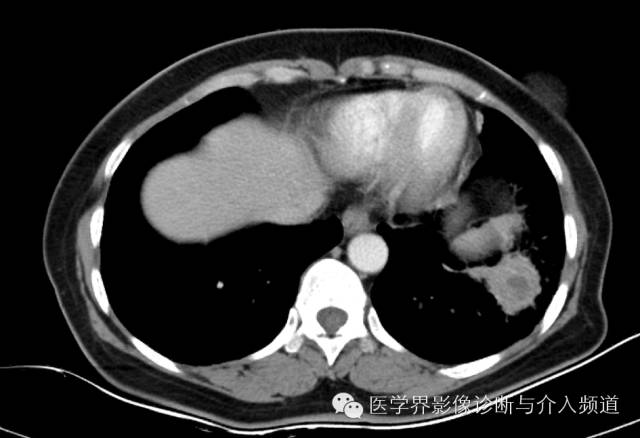

左下肺硬化性血管瘤1例CT影像表现

左肺下叶可见软组织密度肿块影,形态不规则,边界不光整,与胸膜粘连不清,周围肺组织呈磨玻璃密度改变,病变内部不均匀强化,低密度区不强化。

硬化性血管瘤

其他征象:钙化、囊变(与出血有关)、周围晕征(非特征性)、周围肺组织肺气肿、增强扫描明显均匀强化(与病变内血管瘤区、乳头区、硬化区、实变区有关)、贴边血管征(肿瘤推挤周围血管,较具特征性)、纵膈及肺门淋巴结(罕见,但有报道)。